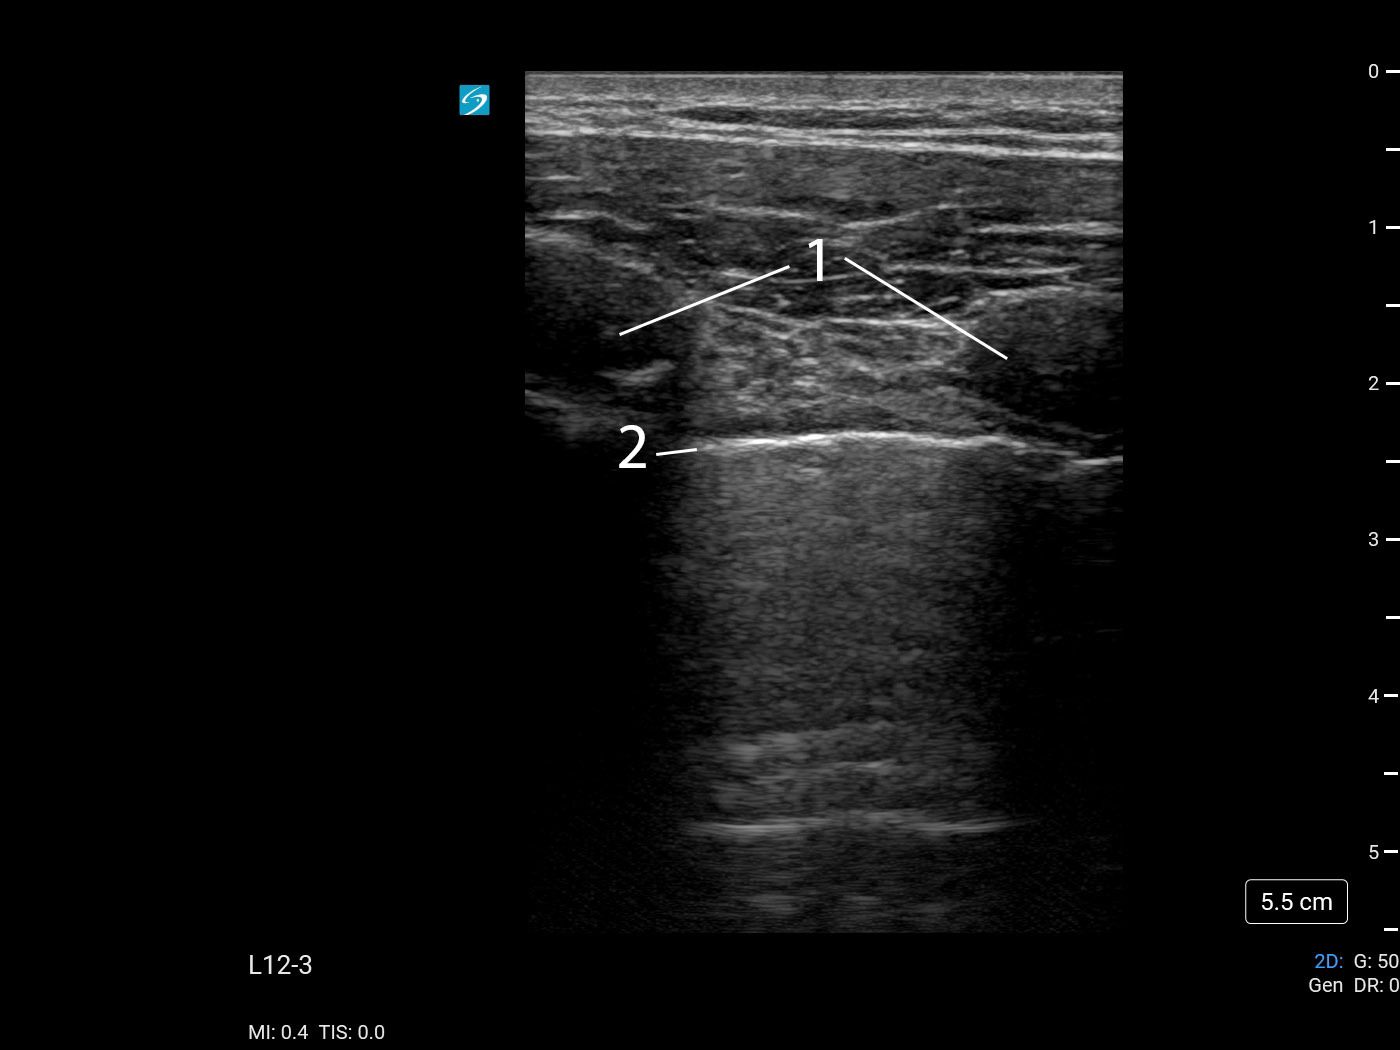

Bild: Lunge, Bewertung der Pleura , Lungenverschiebung 3

Rippen

Pleuralinie